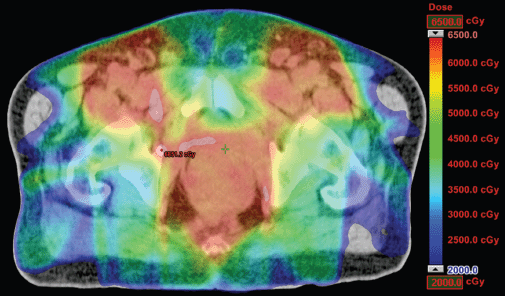

The IMRT achieved better dosimetric results in all organs tested in both the male and female patients. Compared with conformal radiotherapy, IMRT dose was reduced by 59% in the bladder, 14% in the intestine, 41% in the genitals, 26% in the iliac wings, 75% in the femoral heads and 14% in healthy tissue. The integral doses for all organs were lower with RapidArc® than with the sliding window IMRT or the conformal radiotherapy (Table 3, Figures 1–5).

Figure 2. Dosimetric results obtained with IMRT.